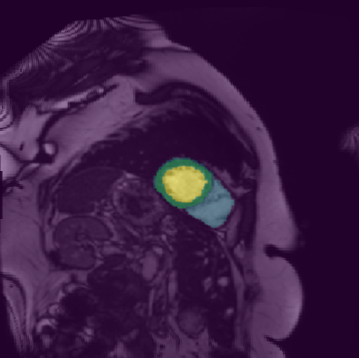

In this paper, we aim to improve the performance of semantic image segmentation in a semi-supervised setting in which training is effectuated with a reduced set of annotated images and additional non-annotated images. We present a method based on an ensemble of deep segmentation models. Each model is trained on a subset of the annotated data, and uses the non-annotated images to exchange information with the other models, similar to co-training. Even if each model learns on the same non-annotated images, diversity is preserved with the use of adversarial samples. Our results show that this ability to simultaneously train models, which exchange knowledge while preserving diversity, leads to state-of-the-art results on two challenging medical image datasets.